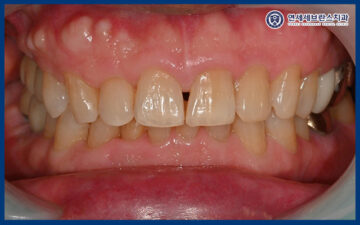

주변 치아와의 자연스러운

색감과 형태를 고려해

조화롭게 완성되었으며,

씹는 기능과 교합 또한 안정적으로 회복되어

일상생활에서 불편함 없이

사용하실 수 있는 상태가 되었습니다.